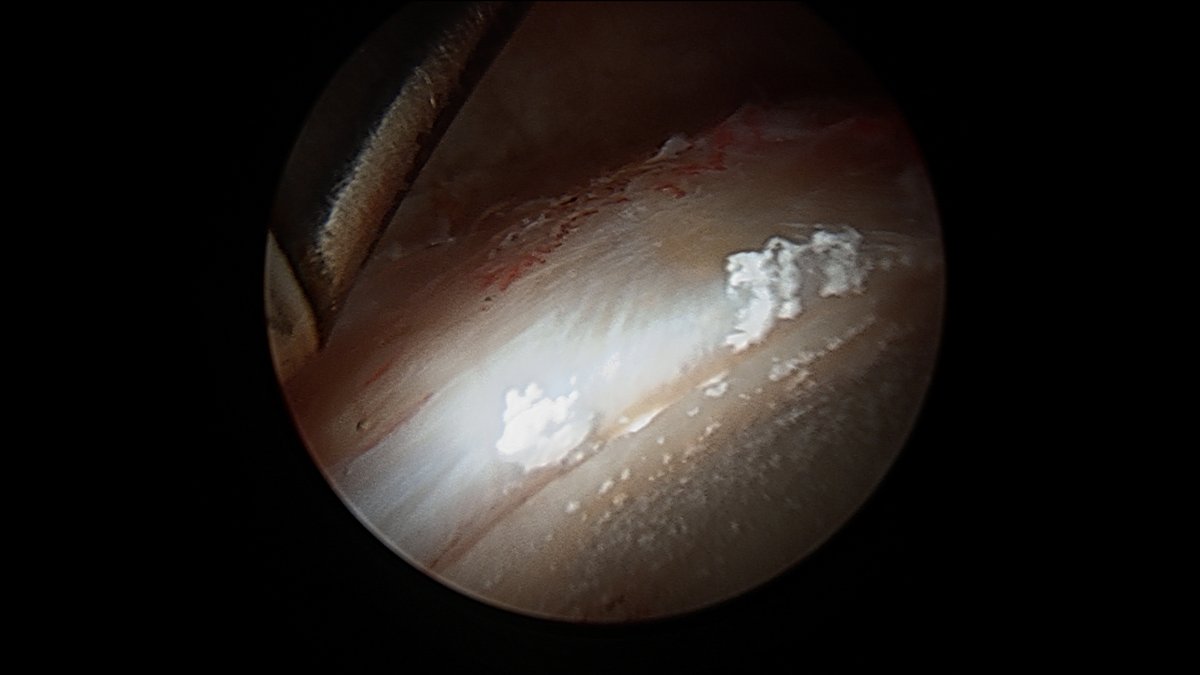

This is chondrocalcinosis isn’t it - not corticosteroid related ? 🤔

This is what a couple previous cortisone injections will look like during #hip #arthroscopy Interesting only on acetabulum, not on femoral head. Do you think these "crystals" (which, by the way, are almost impossible to get out without removing the cartilage) are a problem?